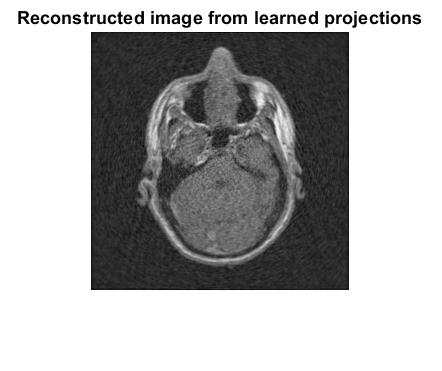

We evaluate the proposed methodology on three different images: the Shepp–Logan phantom, a human head, and a human abdomen. The human images were taken from the public dataset of the National Library of Medicine, as reported in Ref. [20]. These three images are shown in Fig. 4.

We compare the proposed methodology with a feed-forward neural network trained via gradient descent and with cubic spline interpolation. The neural network has hidden layers, taking the projection angle as input and producing the corresponding projection as output. Training is performed on the training dataset, and inference on the learned dataset generates sinograms from both the neural network and the cubic spline interpolation. These sinograms are then used to reconstruct the tomographic image with the Filtered Back Projection (FBP) algorithm. All numerical implementations were written in Matlab, and the code is available in the GitHub repository [21].

In Figures 5, 7, and 9, we present the sinograms, and in Figures 6, 8, and 10 the corresponding tomographic reconstructions of the Shepp–Logan phantom, a human head, and a human abdomen, respectively. Each figure shows results obtained from: (i) sparse projections using only the training samples, (ii) interpolation of the projections with the proposed methodology, (iii) interpolation of the projections with a feed-forward neural network, and (iv) interpolation of the projections with cubic spline interpolation. Columns (left to right) correspond to cases (i)–(iv), while rows (top to bottom) correspond to reconstructions obtained with 50, 100, and 150 training samples, respectively.

In addition, Tables 2, 3, and 4 report the squared error, computed as the Frobenius norm of the difference between the original image and the reconstructed approximations. This error provides a quantitative measure of the reconstruction quality for the Shepp–Logan phantom, the human head, and the human abdomen. The results show that the Learned column, corresponding to the proposed methodology, consistently achieves a lower mean squared error (MSE) than the reconstructions obtained from sparse training data, the feed-forward neural network (FNN), and cubic spline interpolation. This confirms that the proposed methodology outperforms the other approaches. The visual comparisons in Figures 6, 8, and 10 further support this conclusion, as the reconstructions in the middle column (proposed method) exhibit higher visual quality. Overall, these results demonstrate the superior performance of the proposed methodology in tomographic image reconstruction, without requiring any a priori knowledge of the sparse dataset.